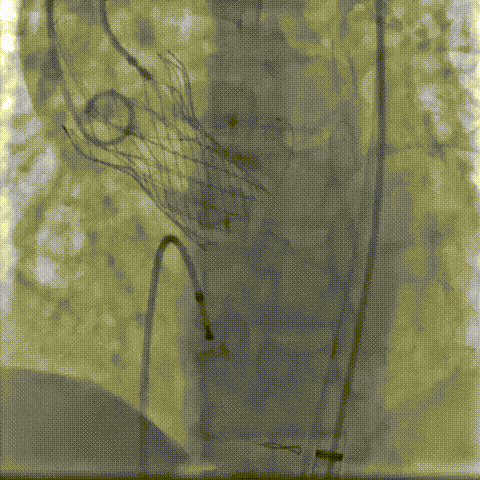

双侧侧髂血管造影血管纤细

LCA保护下18mm球囊预扩,扩张充分,瓣叶向LCA开口偏移;输送器过弓顺利。